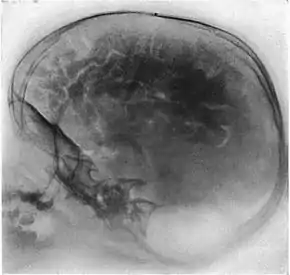

Pneumoencephalography (sometimes abbreviated PEG; also referred to as an "air study") was a common medical procedure in which most of the cerebrospinal fluid (CSF) was drained from around the brain by means of a lumbar puncture and replaced with air, oxygen, or helium to allow the structure of the brain to show up more clearly on an X-ray image. It was derived from ventriculography, an earlier and more primitive method where the air is injected through holes drilled in the skull.

Pneumoencephalography makes use of plain X-ray images. These are very poor at resolving soft tissues, such as the brain. Moreover, all the structures captured in the image are superimposed on top of each other, which makes it difficult to pick out individual items of interest (unlike modern scanners which are able to produce fine virtual slices of the body, including of soft tissues). Therefore, pneumoencephalography did not usually image abnormalities directly, rather their secondary effects. The overall structure of the brain contains crevices and cavities which are filled by the CSF. Both the brain and the CSF produce similar signals on an X-ray image. However, draining the CSF allows for greater contrast between the brain matter and the (now drained) crevices in and around it, which then show up as dark shadows on the X-ray image. The aim of pneumoencephalography is to outline these shadow-forming air-filled structures so that their shape and anatomical location can be examined. Following the procedure, an experienced radiologist reviews the X-ray films to see if the shape or location of these structures have been distorted or shifted by the presence of certain kinds of lesions. This also means that in order to show up on the images, lesions have to either be located right on the edge of the structures or if located elsewhere in the brain, be large enough to push on surrounding healthy tissues to an extent necessary to cause a distortion in the shape of the more distant air-filled cavities (and hence more-distant tumors detected this way tended to be fairly large).